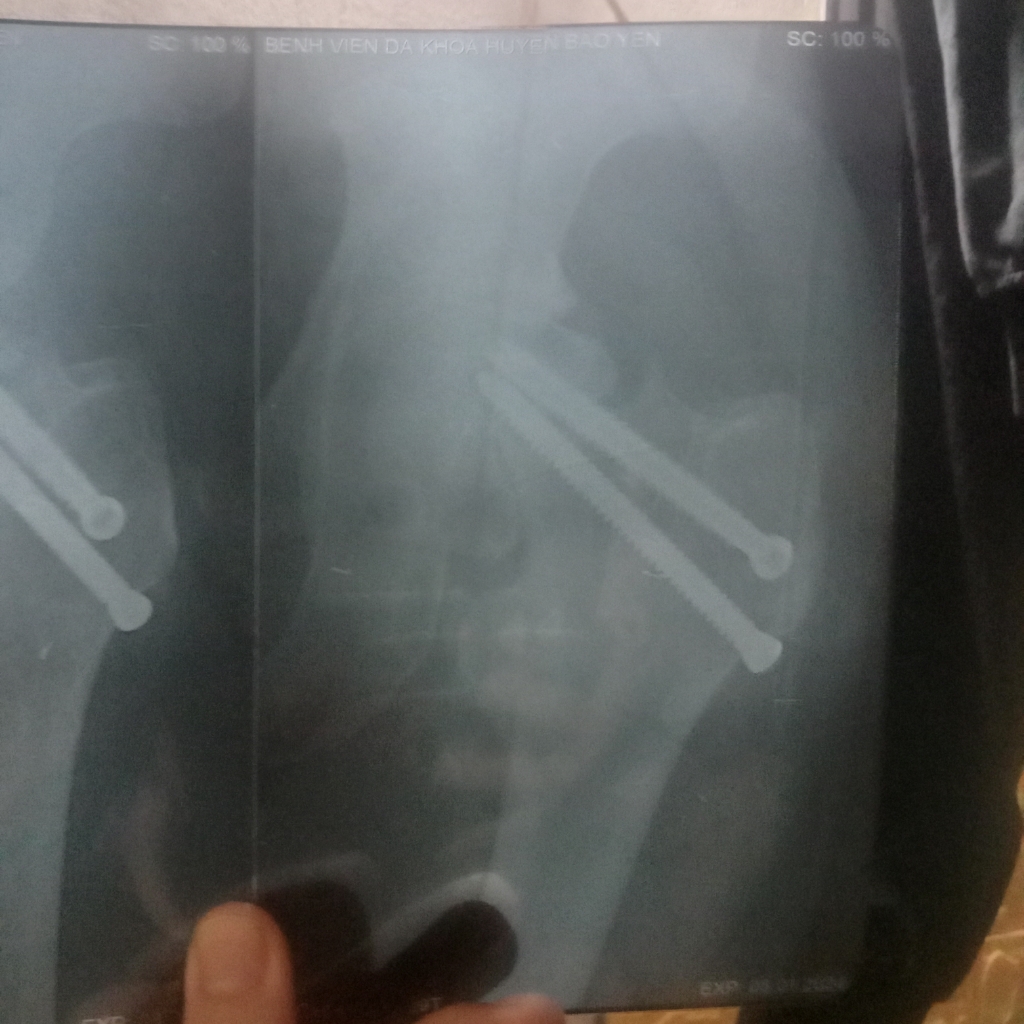

Đây là hình ảnh vít đinh của em ạ. Em thấy nó lệch lệch hay sao ạ bác sĩ.

15/03/2024